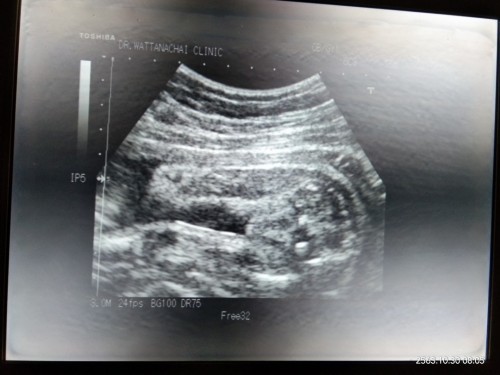

อยากรู้ว่า...

แบบนี้ได้ผู้หญิงหรือผู้ชายคะ

ญ ค่ะ